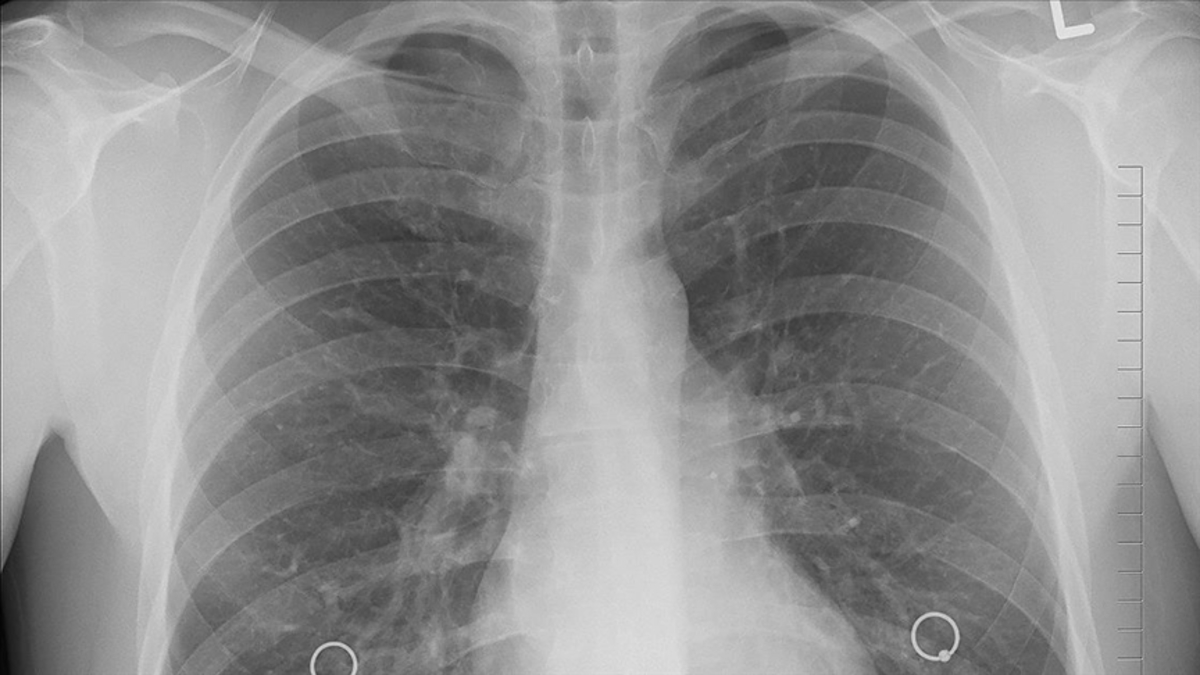

Akciğer kanseri, akciğerlerdeki hücrelerin anormal bir şekilde büyüyüp çoğalarak tümör oluşturduğu bir kanser türüdür. Dünya genelinde en yaygın kanser türlerinden biri olup, genellikle sigara içenlerde görülse de, sigara içmeyenlerde de ortaya çıkabilir. Uzmanlar, akciğer kanserinin erken evrelerinde cerrahi tedavinin en etkili yöntem olduğunu belirtiyor.

Bu kanser türünün küçük hücreli (yulaf hücreli) akciğer kanseri ve küçük hücreli olmayan akciğer kanseri olmak üzere ikiye ayrıldığını söyleyen Göğüs Cerrahisi Uzmanı Doç. Dr. Oktay Aslaner, cerrahi tedavinin, kanserin erken evrelerinde ve belirli şartlar altında uygulandığında hayat kurtarıcı bir rol üstlendiğini belirterek önemli bilgiler veriyor.

Genellikle kanserin akciğerin tek bir bölgesinde sınırlı olduğu, lenf düğümlerine veya uzak organlara yayılmadığı durumlarda cerrahi tercih edildiğini anlatan Doç. Dr. Aslaner, "Cerrahi tedavi, kanserli dokunun olduğu akciğer bölümünün tamamen çıkarılması amacıyla yapılır ve genellikle küçük hücreli olmayan akciğer kanseri vakalarında uygulanır. Küçük hücreli akciğer kanseri vakaları ise hızlı yayılma eğiliminde oldukları için genellikle cerrahi tedaviye uygun değildir" dedi.